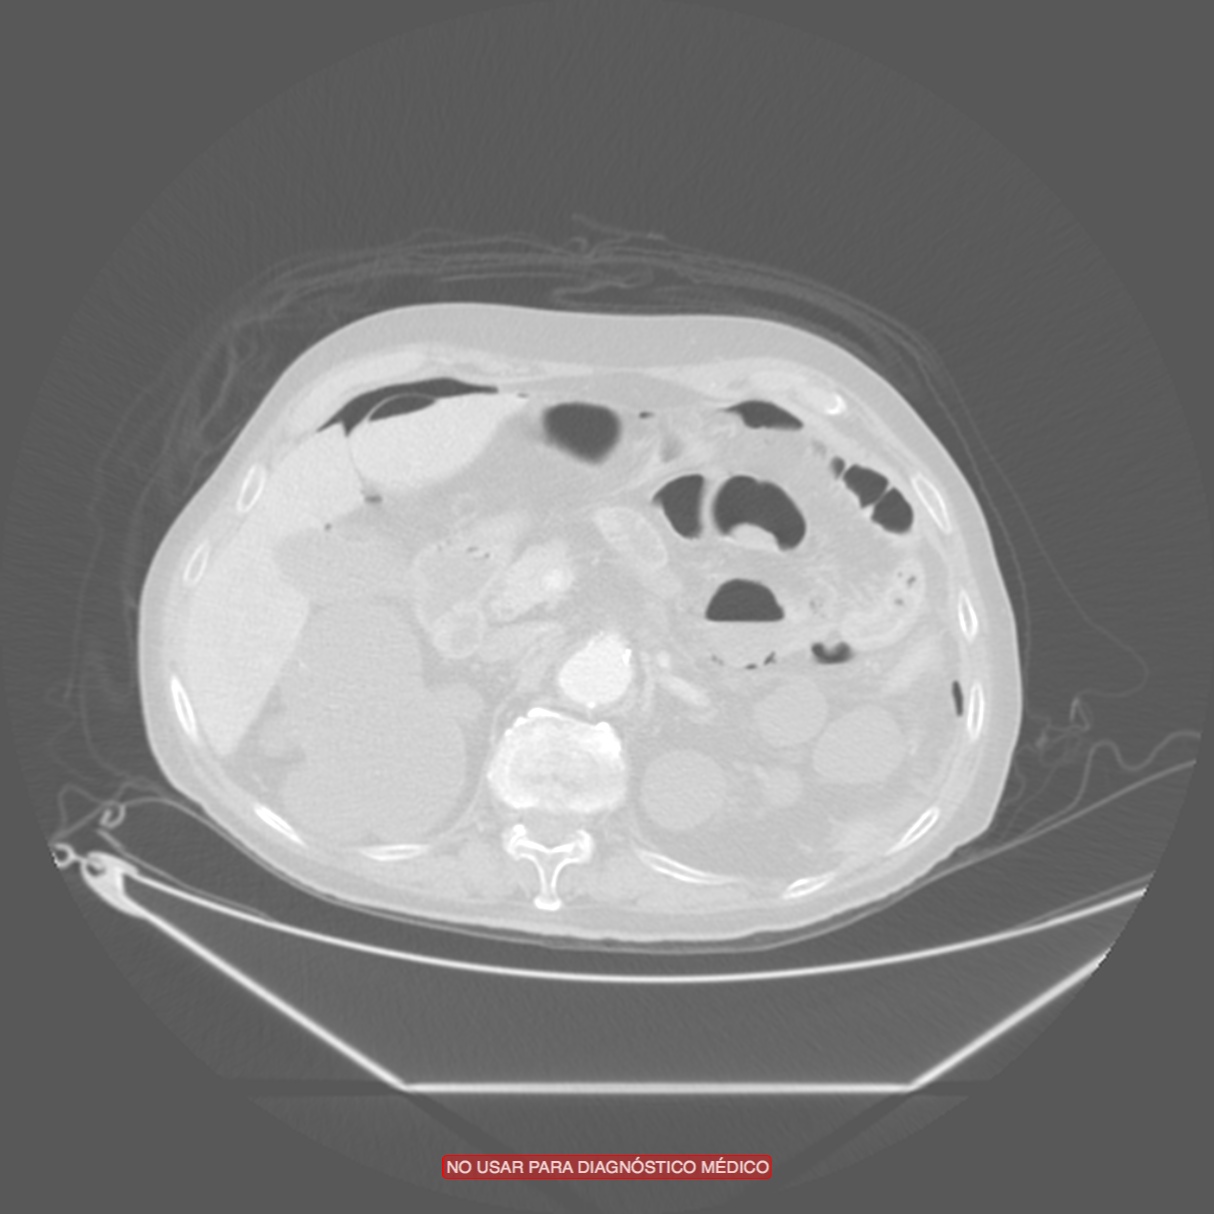

Paciente con diarrea y vómitos y dolor abdominal intenso. Antecedentes de fibrilación auricular. Analítica con discreta leucocitosis.

Se sospecha Isquemia intestinal. Veamos las pruebas complementarias de imagen:

En conclusión, estamos ante un cuadro de posible isquemia intestinal perforada, de ahí el neumoperitoneo.